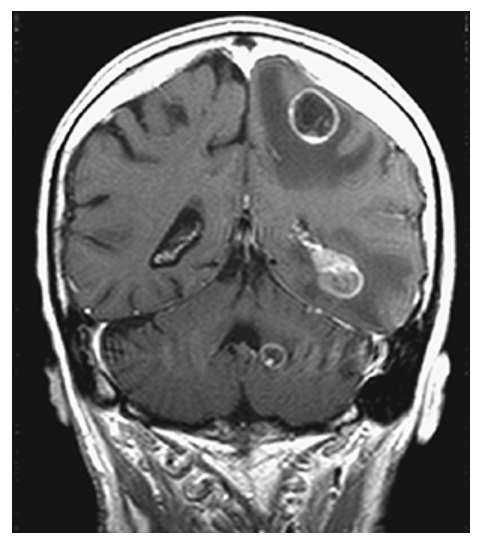

Brain Metastasis. Postcontrast T1W coronal MR shows multiple enhancing lesions with surrounding low-signal edema involving the gray-white junction, white matter, and cerebellum.